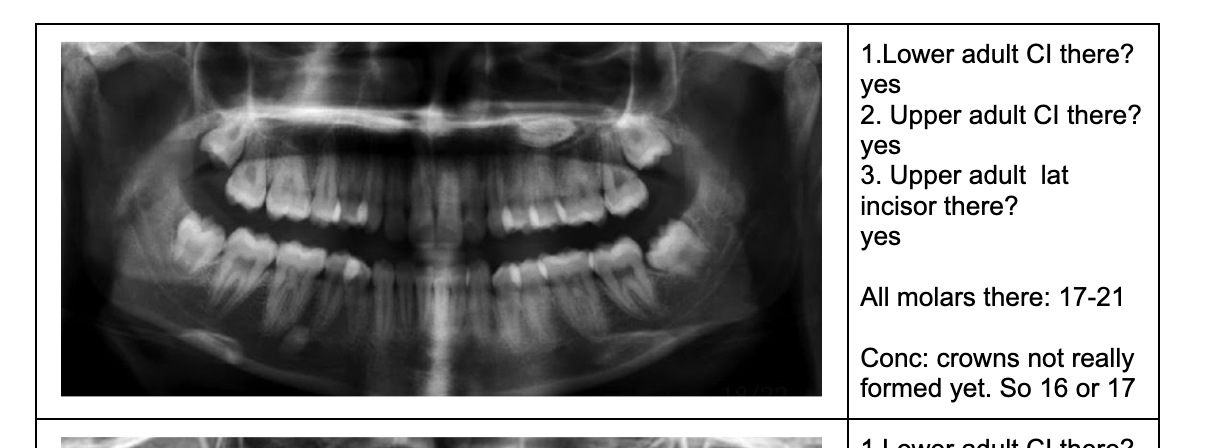

1.Lower adult CI there? YES. so def 6-7

1. Upper adult CI there (they normally erupt 7-8)? NO, baby ones should shed at 6-7.

Conc: pt. Is 6 y.o